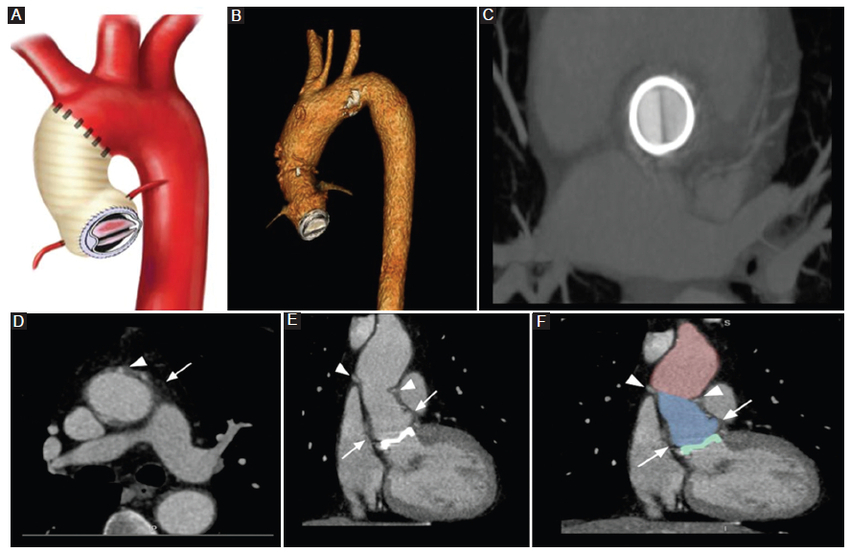

Fue desarrollada para pacientes con enfermedad valvular y dilatación de los senos de Valsalva cuyas paredes eran demasiado vulnerables para permitir la sutura de la prótesis. Consiste en el uso de un injerto compuesto que contiene una prótesis valvular aórtica y el reemplazo protésico de la arteria aorta ascendente, a la que se reimplantan las arterias coronarias nativas (Fig. 2) (2,3,5. Consecuente al desarrollo relativamente común de pseudoaneurismas en los sitios de anastomosis de las arterias coronarias nativas, se produjeron mejoras en la técnica que llevaron a la creación del procedimiento de Bentall modificado o «botón de Bentall», en el que se adquiere un botón coronario de la aorta que contiene el ostium de las arterias coronarias junto a esta, facilitando así la anastomosis del injerto (Fig. 3) (2,3,5. En la actualidad, el botón de Bentall es el método preferido para la reparación de la raíz aórtica. A pesar de estos últimos cambios, no está exento de la formación de pseudoaneurismas en los sitios de la anastomosis aórtica distal2,3,5.

Cirugía de Cabrol

La técnica de Cabrol se desarrolló como una alternativa al procedimiento de Bentall modificado en pacientes con disección aórtica, aneurisma aterosclerótico e imposibilidad de realizar la técnica de Bentall por aterosclerosis grave que impide el empleo de botones aórticos, así como el compromiso grave de la arteria coronaria proximal. Primero, los ostia coronarios se anastomosan a un conducto protésico en una anastomosis término-terminal. A su vez, este conducto está anastomosado al injerto aórtico ascendente en una anastomosis latero-lateral, típicamente posterior al injerto (Fig. 4) (2,3,5. La apariencia posoperatoria normal de un conducto retroaórtico puede asemejarse a un colgajo de disección aórtica, por lo que el conocimiento de la técnica quirúrgica y su antecedente es importante al momento del informe imagenológico2,3,5.